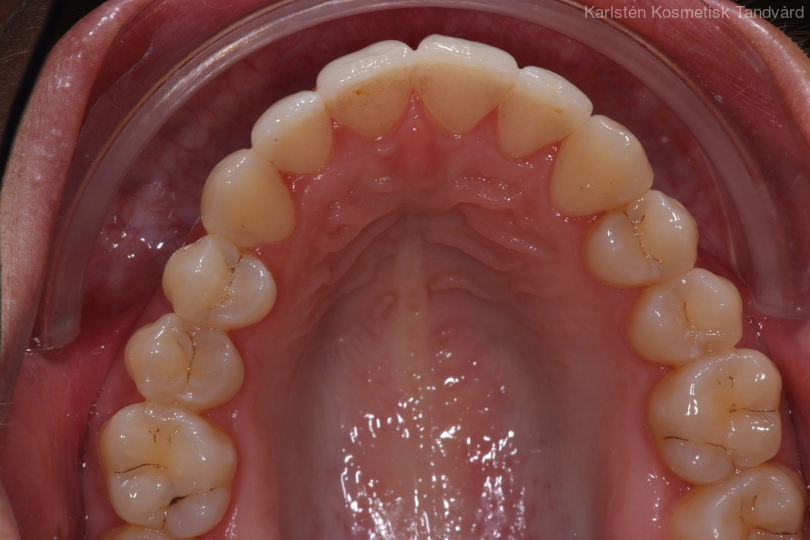

Tandreglering 1

Ung kvinna som tidigare haft tandreglering. Upplever inte att tänderna står i en fin tandbåge. 11 månaders behandling med genomskinliga Invisalignskenor resulterade i ett fint leende.